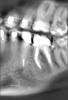

Oleg-Gru Опубликовано 8 апреля, 2013 Поделиться Опубликовано 8 апреля, 2013 (изменено) Здравствуйте! Полтора года назад был пролечен 36 зуб, закрыта старая перфорация коронковой части, пройдены каналы, сверху накрыто МК. На данный момент видимого ухудшения состояния этого зуба нет. Месяц назад, по ортодонтическим причинам, было сделано КТ. Интересует текущее состояние шестерки.Как вы думаете, каков ресурс у этого зуба? Пару-тройку лет протянет? Заранее благодарен! Изменено 8 апреля, 2013 пользователем Oleg-Gru Ссылка на комментарий

DmitrySH Опубликовано 9 апреля, 2013 Поделиться Опубликовано 9 апреля, 2013 Зачем прицельный снимок? КТ не очень хорошее. Пломбировочный материал сильно фонит и портит картину. Ссылка на комментарий